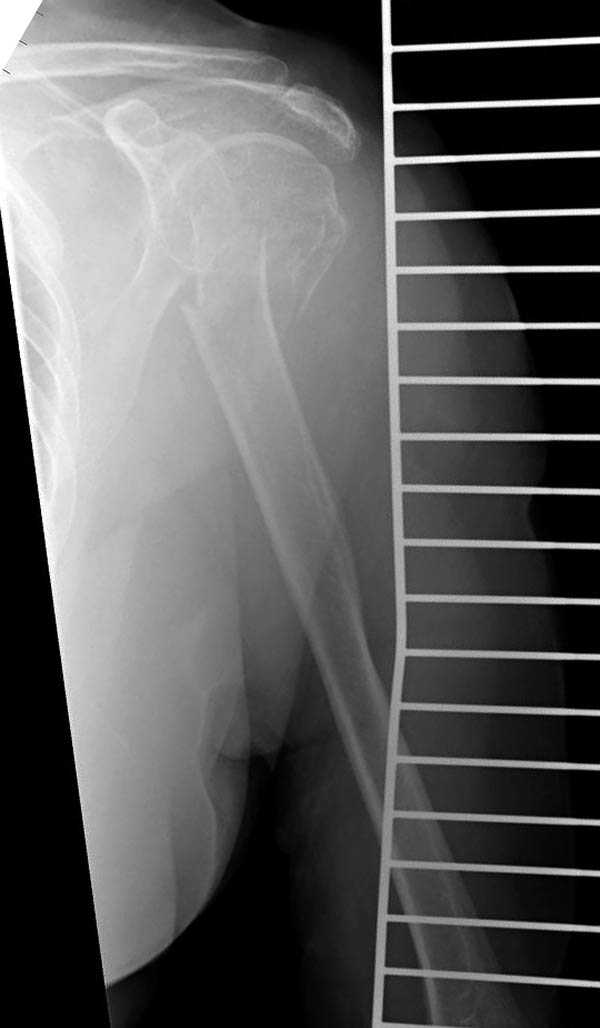

На 20-е сутки снял гипс, одел фиксирующюю

ортопедическую повязку. Вот контроль. Как видно, стояние хорошее, уже формируется костный мозоль.

Думаю еще недели 3 продолжать фиксацию.

-Головка плеча в небольшом варусе или это

проекционное?

Да, там имеем небольшой варус, надеемся, что в будущем проблемы не будет.